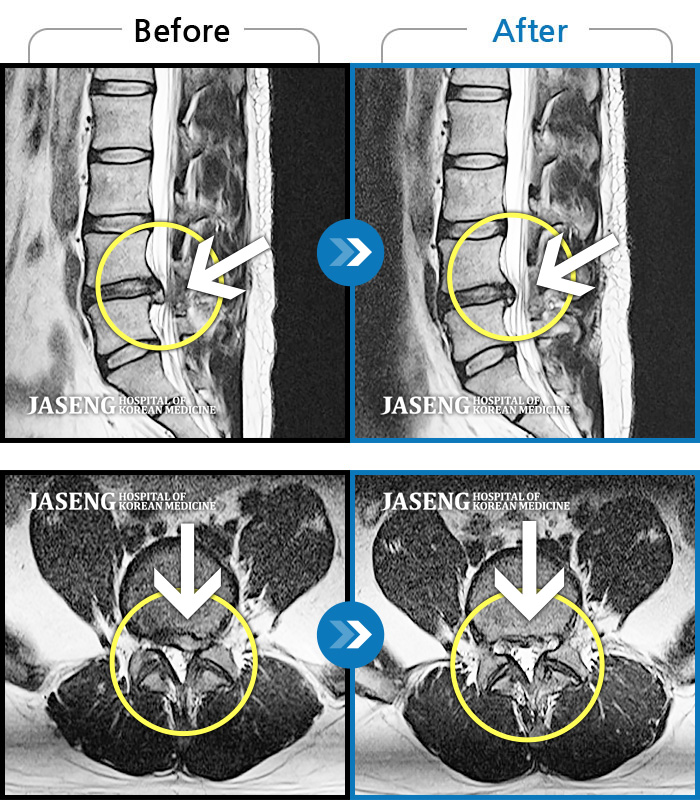

Before

After

환자에게 사전 동의를 받아 동일 조건에서 촬영되었습니다.

개인에 따라 치료 후 부작용이 발생할 수 있으니 의료진과 상담 후 치료를 진행하시기 바랍니다.

디스크로 인한 좌측 하지 통증 재발

허리에서 골반으로 내려가는 심한 통증, 바로 눕기 어려운 상태